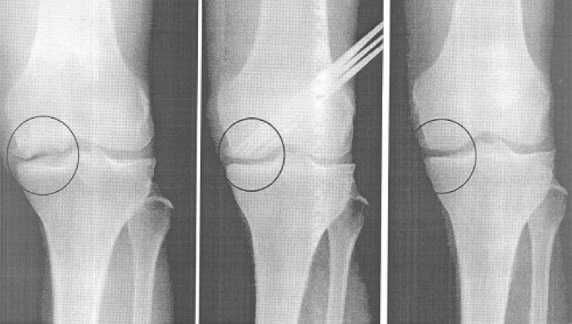

Артродез коленного сустава проводится преимущественно внутрисуставным способом:

- На передней поверхности колена осуществляется полукруглый разрез, который огибает коленную чашечку снизу;

- Отводят её в сторону, удаляют хрящи и внутрисуставные связки;

- Кости иссекаются так, что бы их поверхности заходили друг в друга, подобно мозаике;

- Надколенник устанавливается в своё анатомическое ложе;

- Мягкие ткани плотно сшиваются, накладывается гипс.

При артродезе коленного сустава голень оставляют слегка согнутой для удобства передвижения пациента после того, как сформируется хирургический анкилоз.